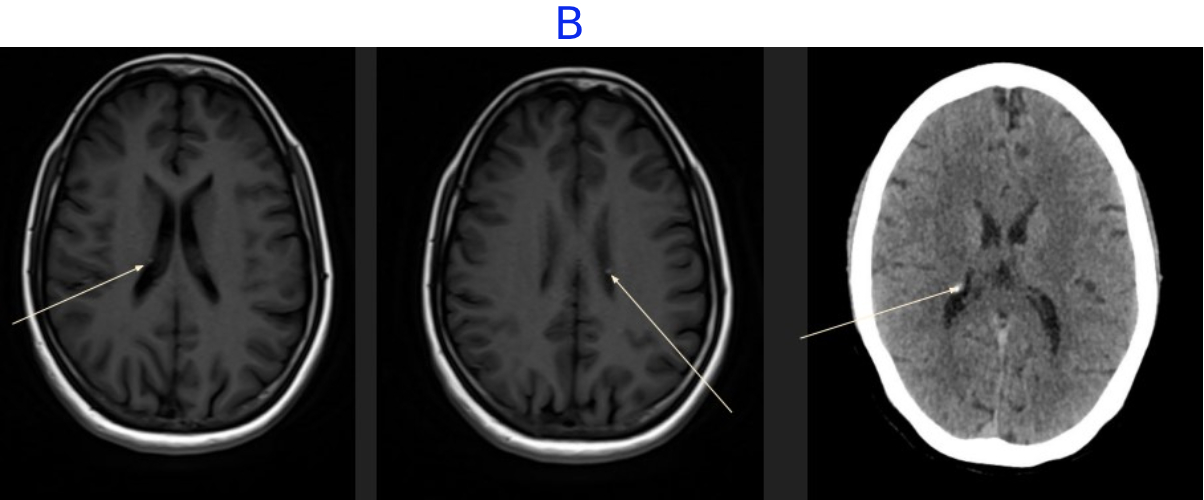

• A. MR BRAIN

• B. Multiple small subependymal nodules are seen along the margins of the bilateral lateral ventricles with few showing calcification on correlative CT.